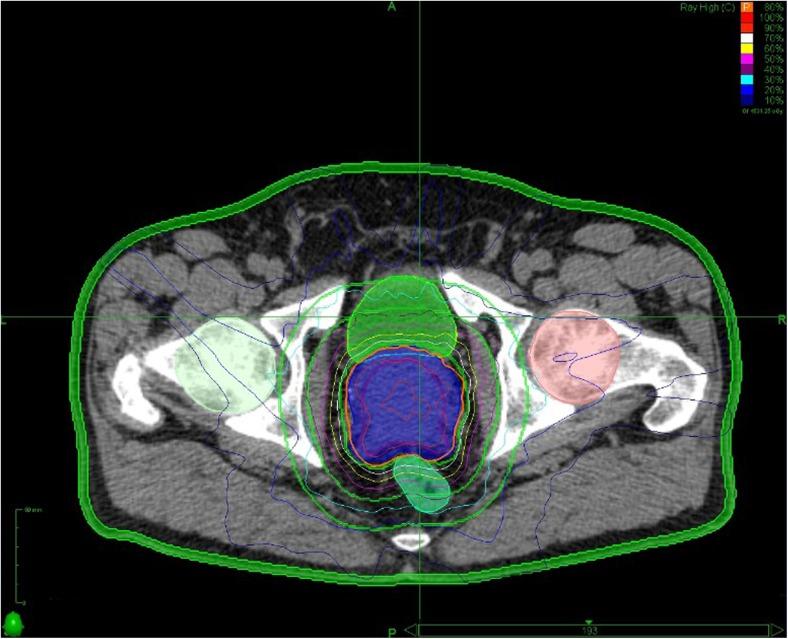

大分割放疗在前列腺癌中的作用。

The Role of Hypofractionated Radiotherapy in Prostate Cancer.

It is now accepted that prostate cancer has a low alpha/beta ratio, establishing a strong basis for hypofractionation of prostate radiotherapy. This review focuses on the rationale for hypofractionation and presents the evidence base for establishing moderate hypofractionation for localised disease as the new standard of care. The emerging evidence for extreme hypofractionation in managing localized and oligometastatic prostate cancer is reviewed.

RECENT FINDINGS

The 5-year efficacy and toxicity outcomes from four phase III studies have been published within the last 12 months. These studies randomizing over 6000 patients to conventional fractionation (1.8-2.0 Gy per fraction) or moderate hypofractionation (3.0-3.4 Gy per fraction). They demonstrate hypofractionation to be non-inferior to conventional fractionation. Moderate hypofractionation for localized prostate cancer is safe and effective. There is a growing body of evidence in support of extreme hypofractionation for localized prostate cancer. Extreme hypofractionation may have a role in managing prostate oligometastases, but further studies are needed.